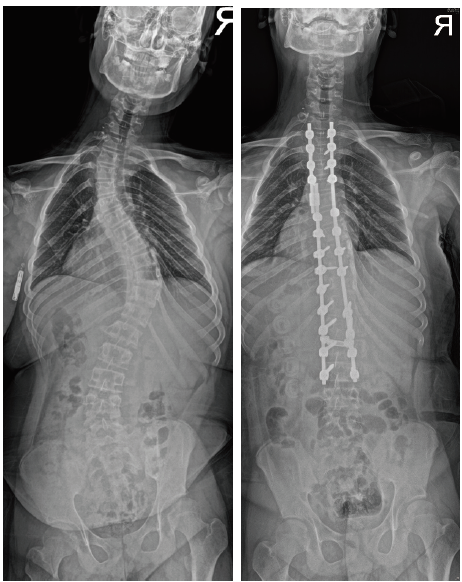

- 허리쪽의 만곡이 심한 경우는 요추의 어느 부분까지 고정 할지가 중요합니다. 고정 범위가 길어지면 교정은 좋아 지지만 움직일 수 있는 허리의 운동 범위가 줄어듭니다. 보통 생활에는 지장이 없지만 허리의 운동 범위를 보존해 주는 것이 좋기 때문에 수술이 필요한 경우에는 만곡이 뻣뻣해 지기 전 적절한 어린 나이에 고정을 해주어 수술 범위를 필요한 부분만 하는 것이 좋습니다.

- 수술 후 어깨의 불균형이 예상되거나 상부 흉추의 만곡이 크고 강직된 경우 상부 흉추의 만곡을 수술에 포함하기도합니다. 목 아래까지 수술이 필요합니다.

- 수술 시 중요한 것은 만곡의 교정과 함께 머리-어깨-골반의 균형을 맞추어 주는 것입니다